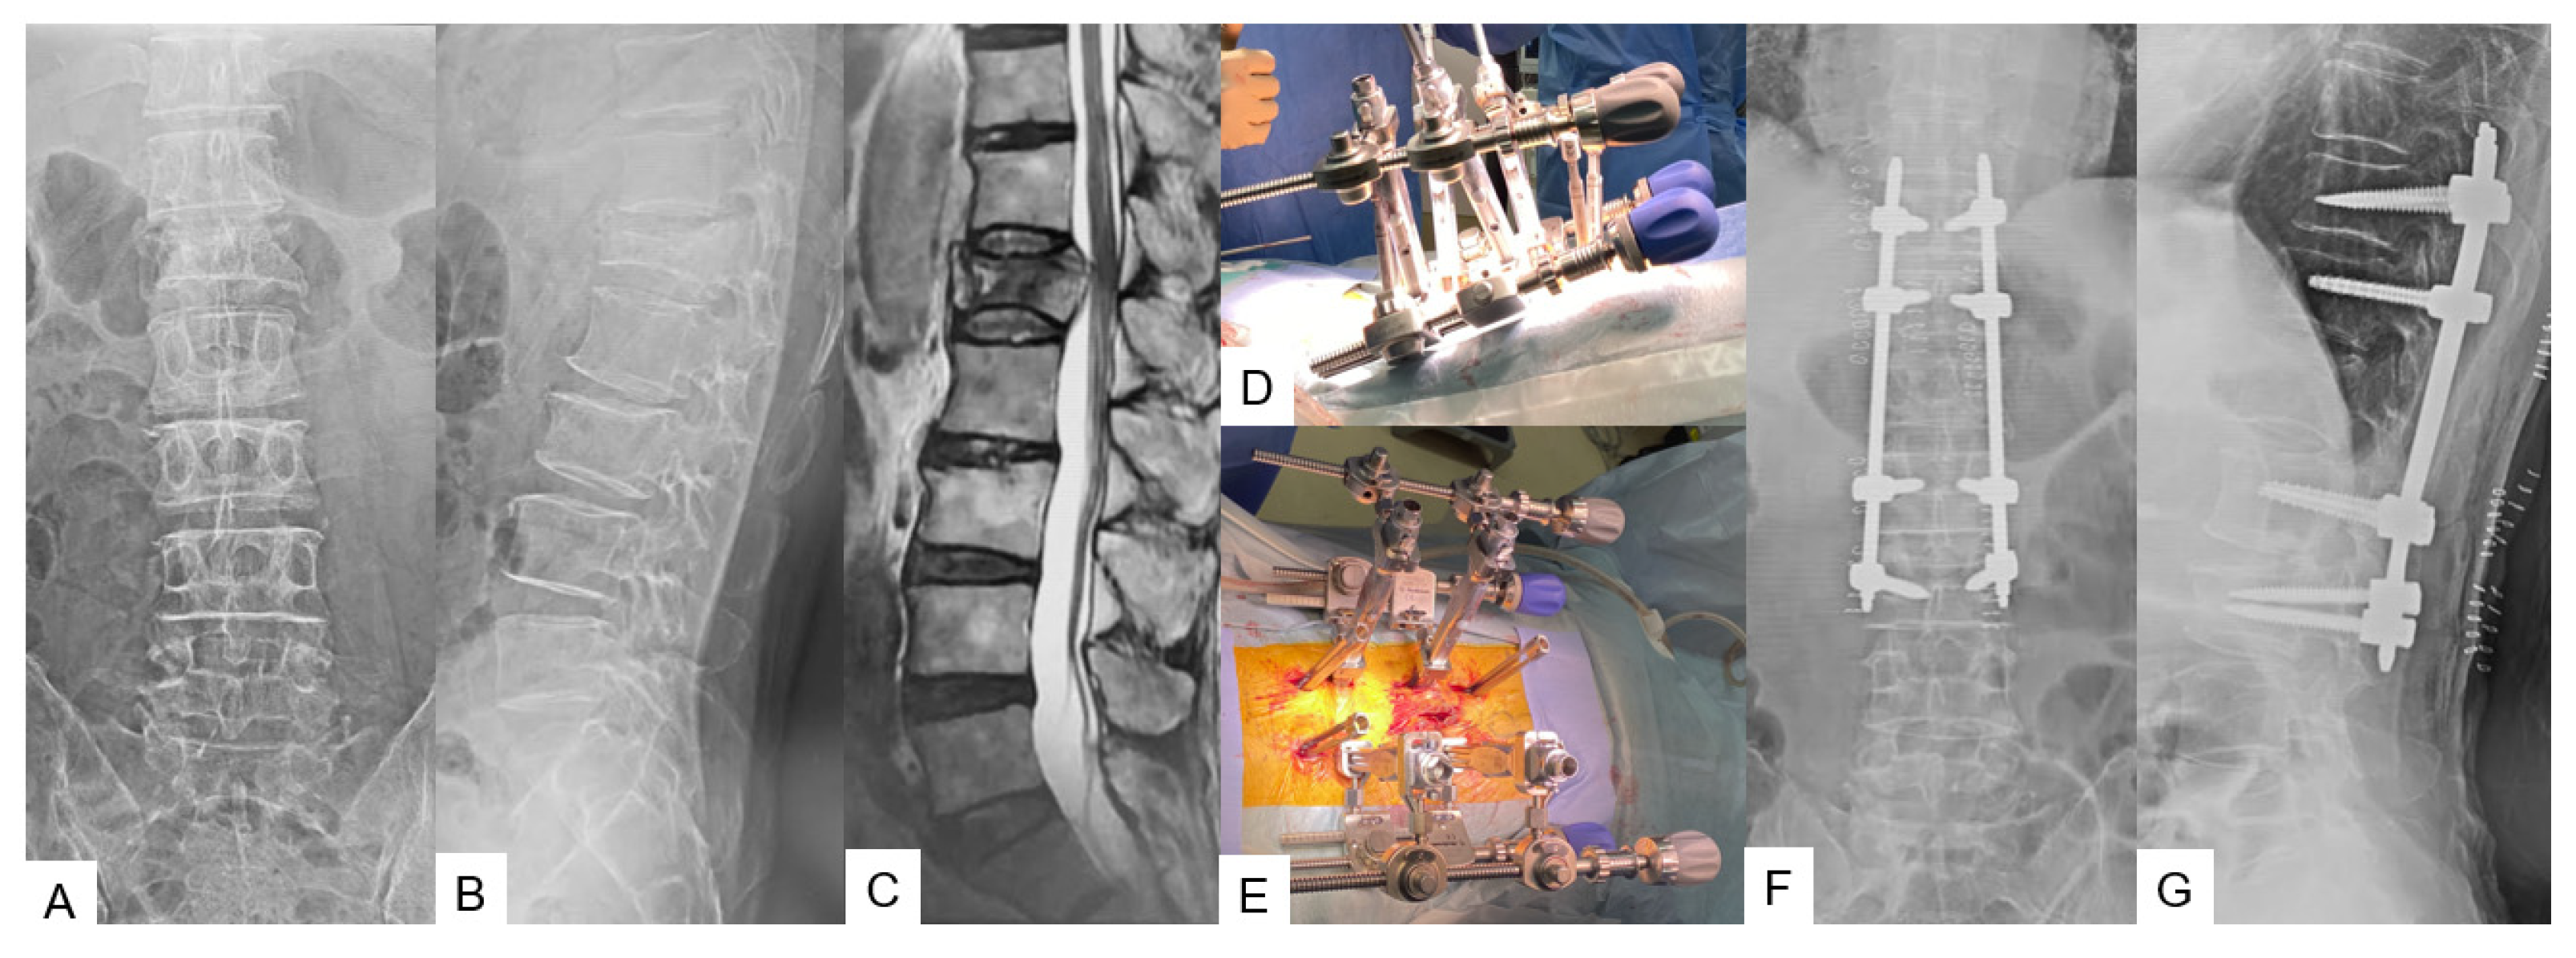

2.2. Thoracolumbar Posterior Application

2.2.2. C-Arm-Free Trauma